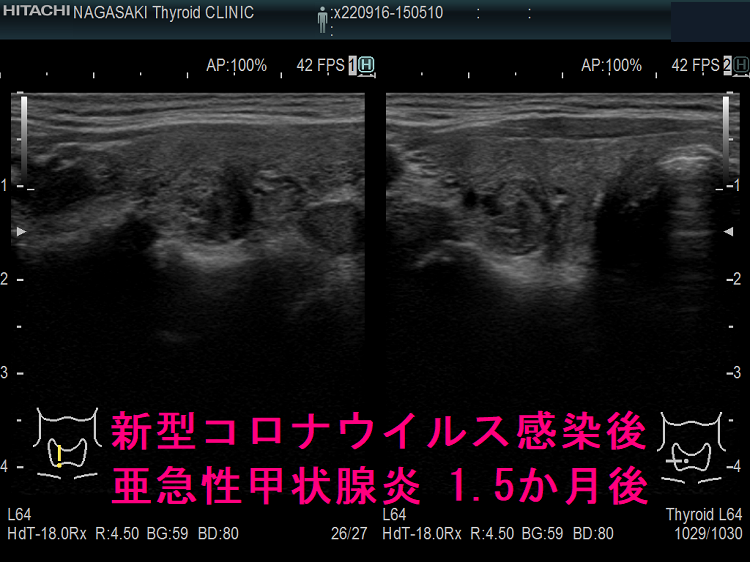

以下は、長崎甲状腺クリニック(大阪)の自験例です。

長崎甲状腺クリニック(大阪)の自験例

1.5か月後